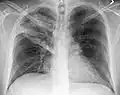

Normal AP CXR